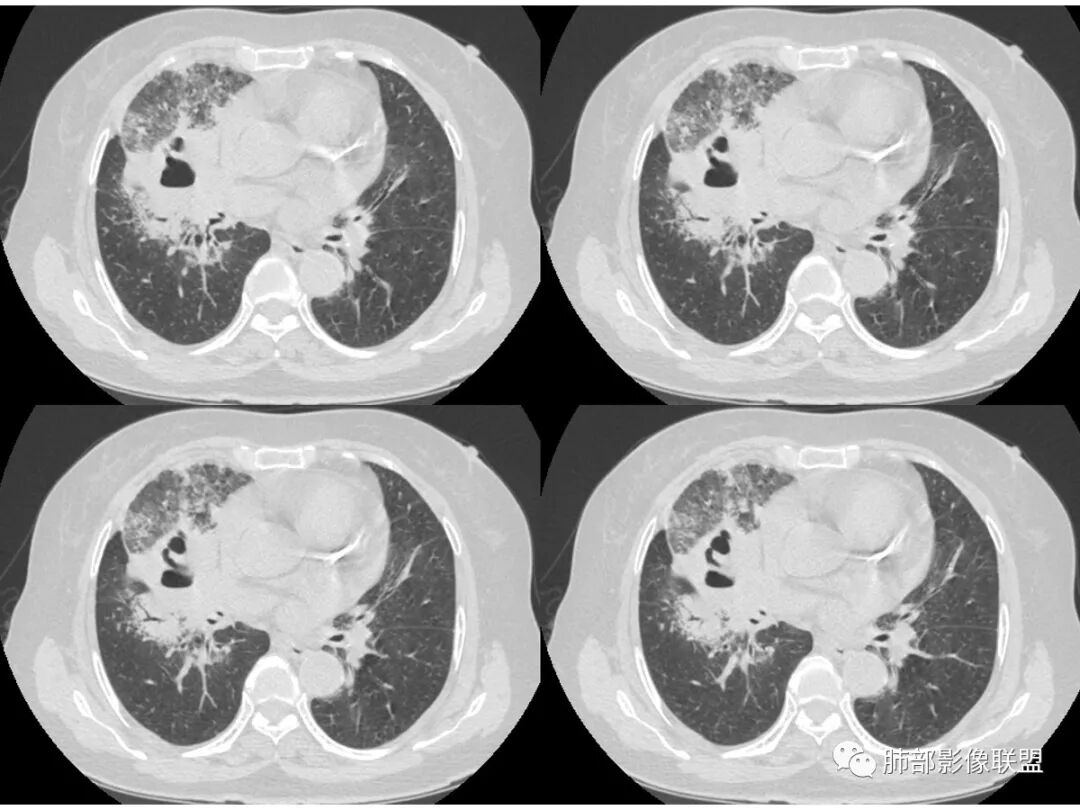

老年女性,右肺上叶大片实变及磨玻璃密度影,磨玻璃边缘清晰,内可见小叶间隔增厚,内可见空洞,似可见分隔,叶间裂局部膨隆,纵膈窗,没有增强,枯树枝不明显,肺炎型肺癌可能,鉴别大叶性肺炎,结核?

胸CT:右肺上叶实变内可见支气管充气征,近端支气管狭窄,远端扩张,周围可见毛玻璃影,右肺中叶支气管闭塞,并可见气道壁钙化,右肺中叶体积缩小,实变内可见空洞,并可见气液平面,空洞周围可见毛玻璃样影,右肺下叶支气管开口狭窄,右肺门淋巴结肿大。纵隔窗可见病灶与壁层胸膜间隙增宽,考虑良性病变-----感染性病变------TB?

右肺上叶病变,内见钙化及空洞,支气管可见,考虑结核伴出血。

右中叶支气管完全阻塞伴厚壁空洞,右上叶支气管不全阻塞伴大片GGN,右下部分GGN考虑腺鳞癌,结核待排。

老年女性,病史1月,白细胞不高,贫血、低蛋白。影像:右肺上叶大片状阴影,支气管大致通畅,内见一空洞和液平,病灶边缘可见磨玻璃影,分布相对集中,边界较清晰,有重力效应。首先考虑良性病变,慢性感染并出血,鉴别粘液性腺癌伴感染。

右肺上叶、中叶大片实变影,实变影边缘较平直,内部可见一空洞液平,壁光整,实变周围斑片磨玻璃影,考虑感染性病变伴出血!

老年女性,慢性病程,咳嗽伴白色粘液痰,无发热腹痛,糖尿病,白细胞及C反应蛋白不高,血沉快,铁蛋白高。胸部CT,右肺上叶大片状实变伴磨玻璃密度影,边界不清,边缘局部膨隆,叶裂弧形下坠,实变影宽基底与胸膜相贴;右肺下叶前基底段见类似病灶;右肺中叶不张并空洞形成,空洞内见气液平面;综合考虑右肺上叶及下叶肺炎型肺癌,右肺中叶结核。

这里是中叶的不张和空洞,有钙化,结核确实也不能排除

主病灶应该是粘腺腺癌,右中叶不张?,内空洞,壁光滑,考虑感染

实变区像支气管爬行征?空洞区也有钙化和边界清楚模玻璃影

1.王老师的病理说明粘液腺癌的破坏力弱,对血管和支气管破坏少,所以理论上空洞少,这个空洞很明确。

3.熊老师告诉我们:肺结核可以有磨玻璃,这个我以前一直不知道,右肺门淋巴结有钙化,病灶内纵膈窗隐约细细点状钙化,所以结核磨玻璃可以,

这个病人可以当做干酪性肺炎的扩大延长版